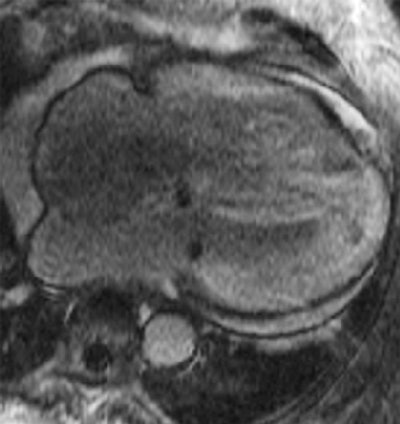

Cardiac late-enhancement MR image in an 80-year-old female with shortness of breath, concentric left ventricular hypertrophy and severe diastolic dysfunction.

By Dr. Chiara Bucciarelli-Ducci, University of Bristol, U.K.